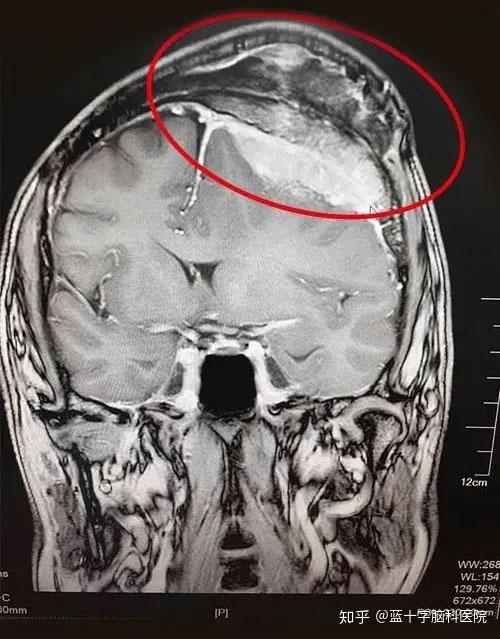

巨大脑膜瘤图例脑部肿瘤,尤其是原发性脑瘤和中枢神经系统恶性肿瘤

图片尺寸500x639